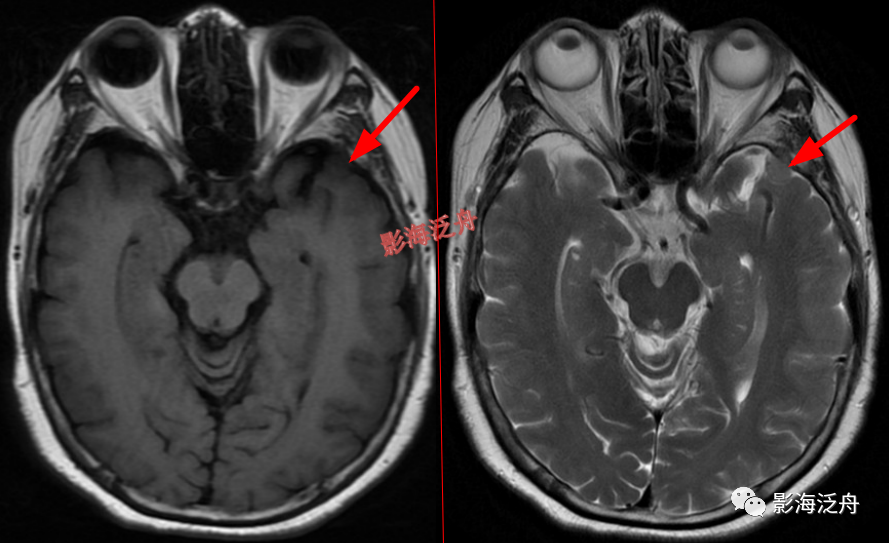

左侧颞部脑膜瘤

,在T1WI、T2WI、Flair、DWI四个序列上都非常接近脑实质的信号。这么小的脑膜瘤在MR平扫上漏诊率极高,避免漏诊的办法就是把颅脑解剖学好,然后看片子的时候把脑沟快速地捋一遍,脑沟发生形态改变的区域重点观察。

延髓左侧小梗死灶。这种斑点状的梗死灶漏诊也非常多见,患者症状一般不明显,我自己漏诊过两次。小的梗死灶多见于脑干、侧脑室周围,大脑皮层区一般不多见。因此,重点区域进行细致观察,可以减少此类疾病的漏诊。